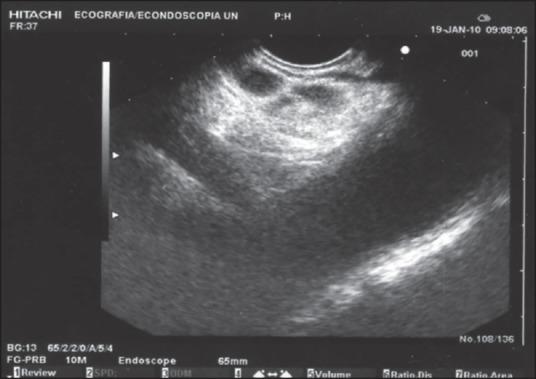

A 75-year-old man suffering from opioid-refractory due to an advanced pancreatic adenocarcinoma was treated with endoscopic ultrasound (EUS)-guided celiac plexus neurolysis (CPN) combined to EUS-guided tumor ablation. No major complications were recorded during the procedure. In the days following the procedure, mild diarrhea and fever were the only minor complications experienced by the patient. Complete tumor devascularization was assessed by means of computed tomography (CT) 48 h after the procedure. The patient remained pain-free without need of opioid, and was treated only with paracetamol for 20 weeks. Our results were optimal in terms of pain relief and immediate tumor response (assessed by means of CT and tumor marker levels). The present case demonstrates that the combined approach (EUS-guided ethanol ablation and CPN) may be a valuable option in patients with pancreatic cancer. Randomized-controlled trials are needed to confirm this result.